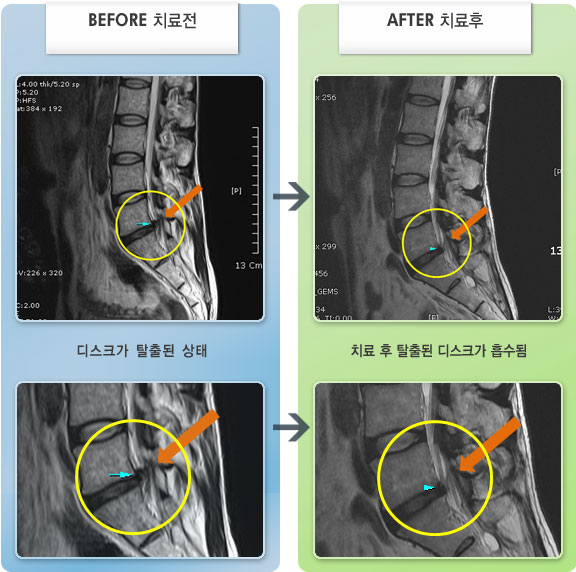

내일이면 퇴원이다. 3월부터 주위에서 허리통증 치료 잘 한다는 통증의학과ㆍ신경외과ㆍ정형외과 병원 3곳을 돌아다니며 허리 신경주사 12번 ,도수치료 10번, 물리치료 등등 정알 여러가지를 받았다. 그러나 치료와 처방 받은 진통제만으로는 일상생활을 하기가 많이 힘들었다. X레이 사진으로 확인한 척추 전방전위증은 결국은 수술을 받아야 한다고 하였다.

전방전위 대해 알아보다가 자생병원 홈페이지에서 김상돈 병원장님이 임상치료 하셨다는 것을 보고 잠시의 망설임도 없이 전화 예약하고 입원 하게 되었다.

MRI 검사로 정확한 진단을 시작으로 병원장님의 치료를 2주간 받았다. 친절한 설명과 따뜻한 배려로 정말 마음 편하게 치료 받을수 있었다.

극심한 통증으로 입원 첫날에 맞은 진통제 주사는 더 이상 필요없게 되었다 다시한번 김상돈 병원장님께 감사 드립니다.

저는 교통사고 후유증과 운동부족,잘못된 자세등으로 간혹 허리가 아팠습니다.. 근데 최근 몇일간 무리한후에 허리가 아프고 왼쪽 하지방사통과 저린감이 너무 심하여 밤에 잠도 제대로 들기 어려울 정도 였습니다...MRI를 찍으니 디스크라고 하더라구요..ㅠ..ㅠ 예상은 하고 있었지만 20대후반에 디스크라니...좌절감과

우울감이 심하였습니다.. 무조건 수술은 안하리라는 생각에 원장님을 찾아뵈었습니다..저한테는 어떻게보면 행운이였나봅니다...

앞으로 치료계획에 대해 상세히 설명해주시며 믿음과 희망을 주셨습니다 ..마음이 한결 가벼워 졌습니다..

추나, 침, 약침, 물리치료, 약물(한약)요법을 병행하며 현재 2주가 조금 지났는데...저도 놀랄정도로 왼쪽 하지방사통은 거의 없어졌어요..감동감동 ㅠ..ㅠ

치료에 대해 믿음이 있었지만 이렇게 빨리 회복이 될지는 저도 놀랐습니다...